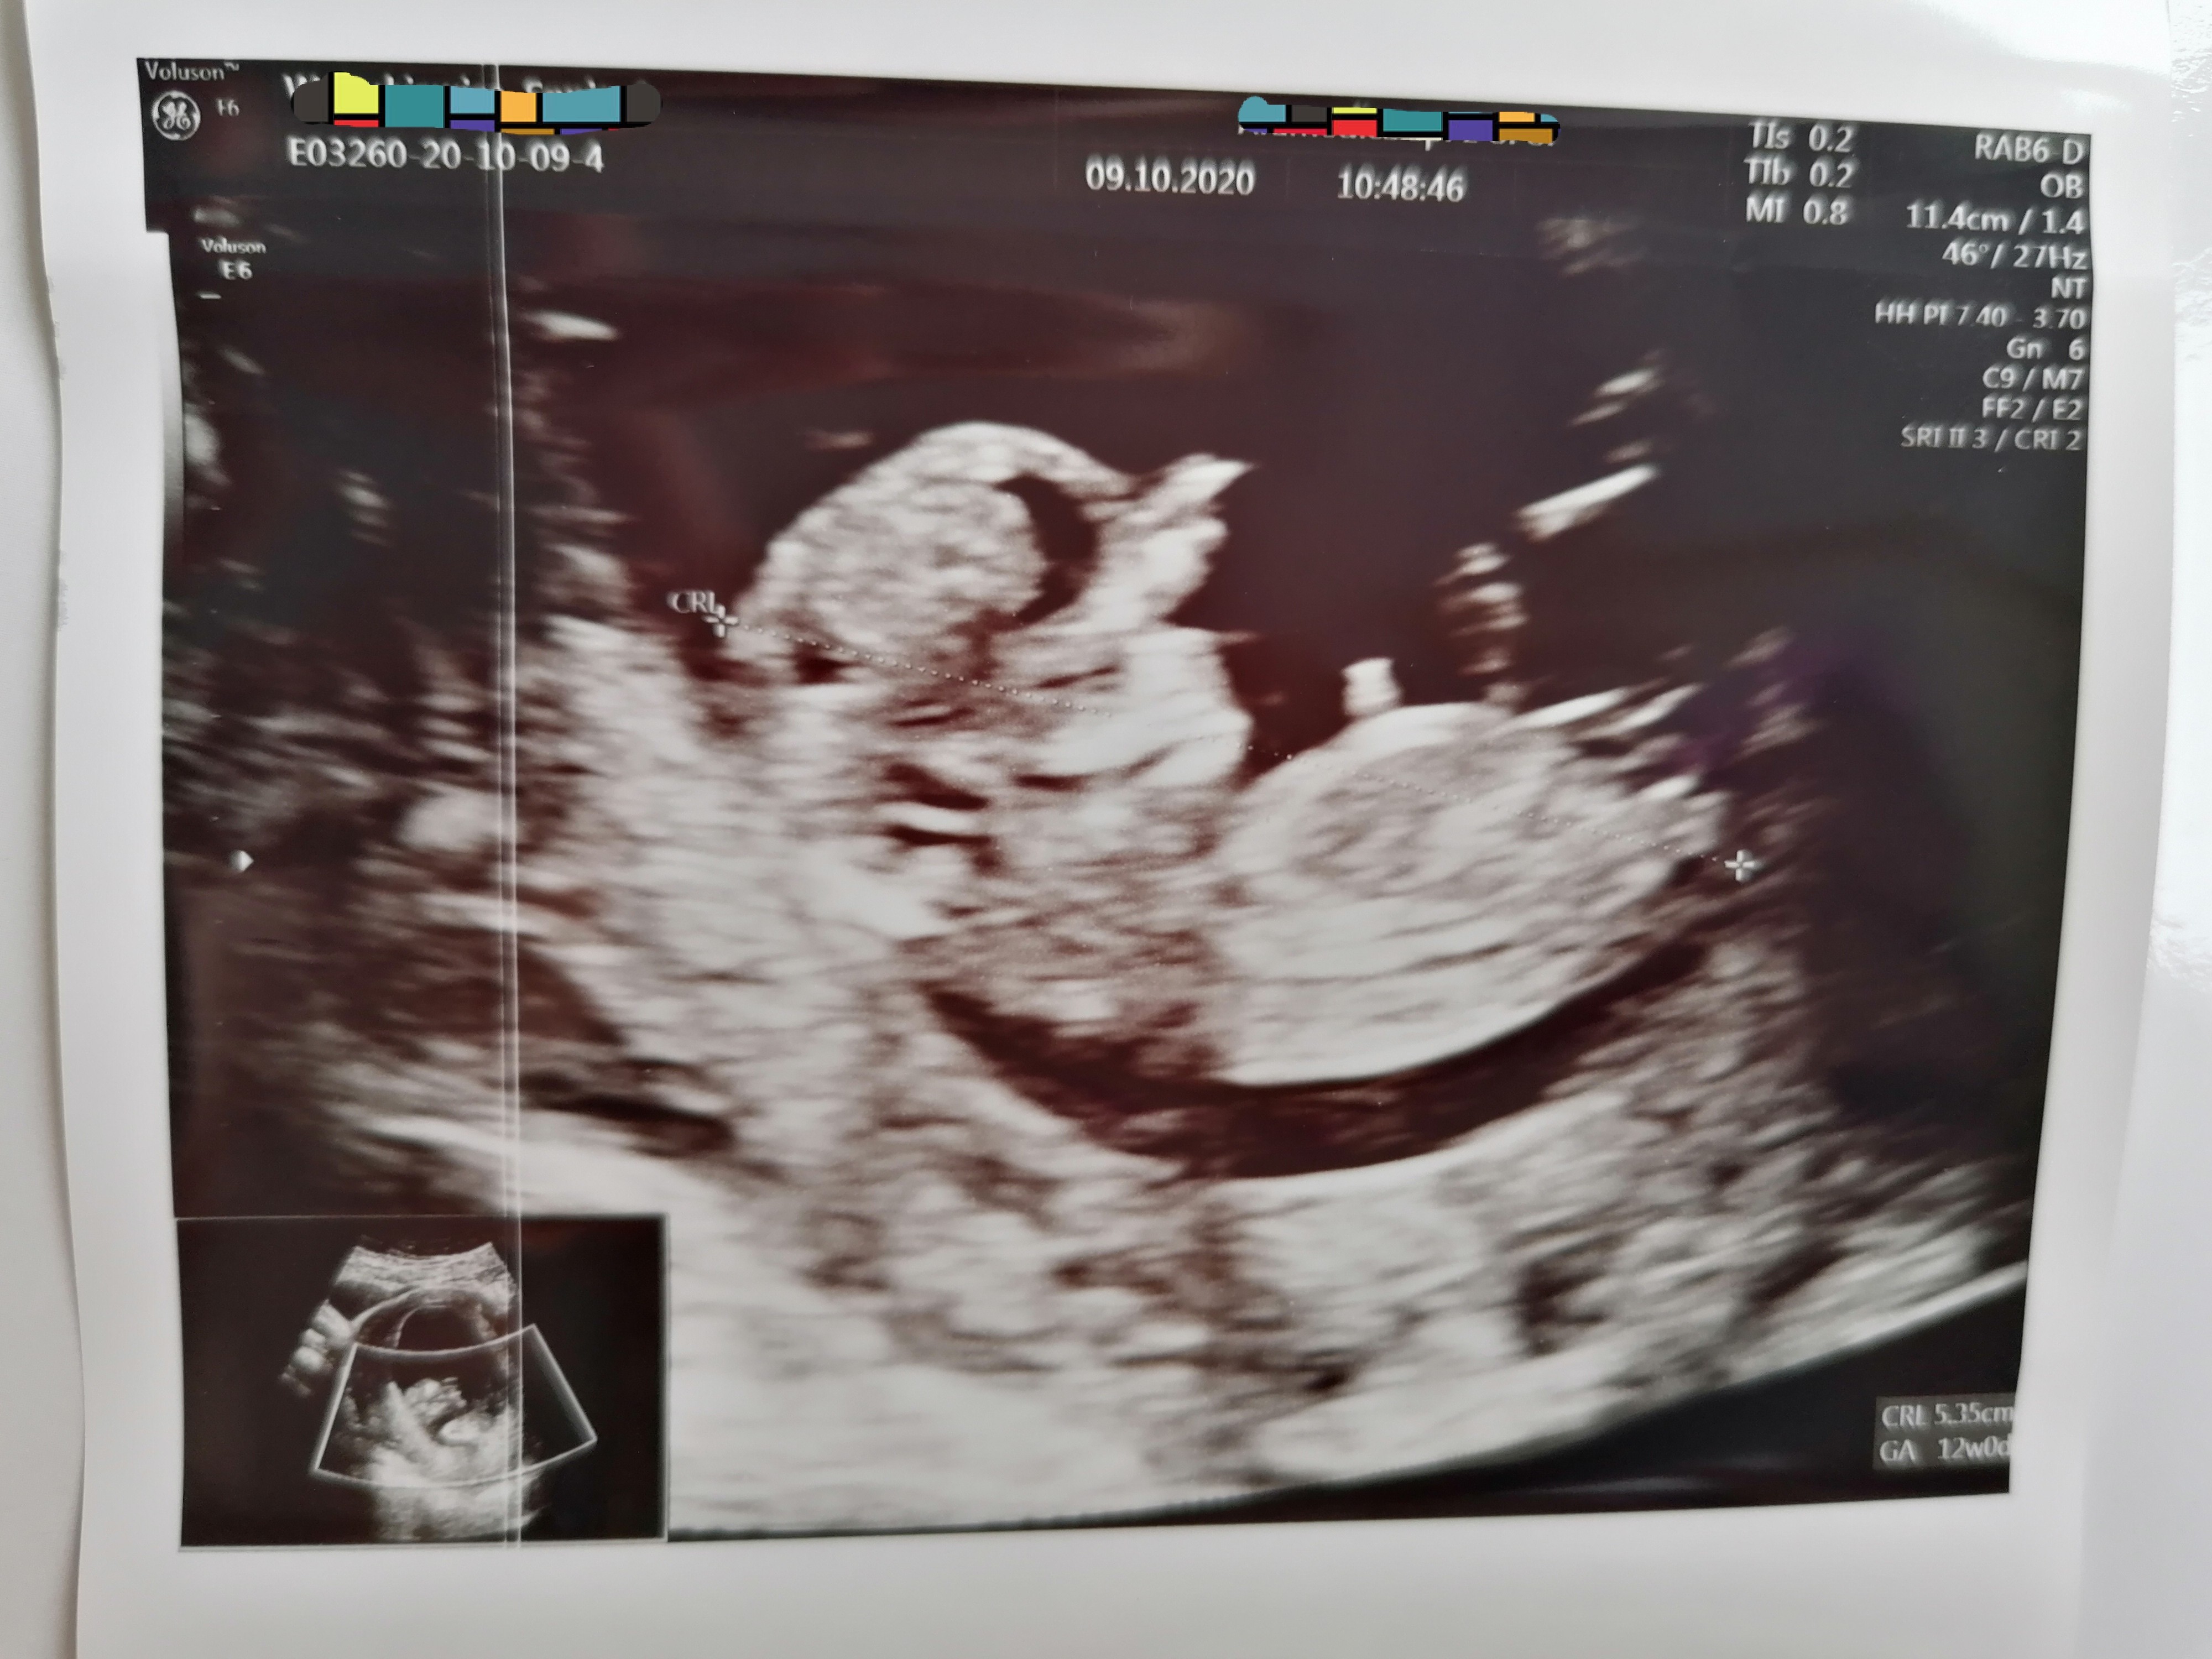

Ahhh cudowne są te dzieciPoproszę męża żeby przyciął filmik i zobaczymy czy można go tu wrzucić?... Zobacz załącznik 1186189Zobacz załącznik 1186189Póki co moje baby na fotografii 2d. 3d też mam![]()

O i to chodzi! Dzidzia❤ rośnie, Mama szczęśliwaJa już po prenatalnych. Wyniki bardzo dobredzidziuś na początku spał, potem machal rączkami i nóżkami, wiercił się tak mocno, że ciężko było lekarzowi zmierzyć przeziernosc. Musiałam zmienić pozycje na chwilę, porozmawialiśmy. Stwierdził, że wyglądam na góra 25 lub 26 lat

mam filmik z całego badania i zdjęcia. Super!

Teraz jeszcze tylko czekamy na potwierdzenie w Nifty. Wynik w poniedziałek a połówkowe 1 grudnia.